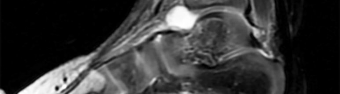

A 14-year-old boy complains of a painful, rigid flatfoot and a history of recurrent ankle sprains. Physical examination demonstrates severe restriction of subtalar motion and peroneal spasticity. A 45-degree internal oblique radiograph of the foot reveals an 'anteater nose' sign. Which of the following is the most likely diagnosis?

Explanation

Question 30

A 13-year-old male presents with recurrent ankle sprains and a rigid, painful flatfoot. Radiographs show an elongated anterior process of the calcaneus resembling an "anteater's nose" on the lateral view. What is the most likely diagnosis?

Question 49

A 12-year-old boy presents with a history of recurrent ankle sprains and a rigid, painful flatfoot. Radiographs demonstrate an "anteater nose" sign.

Which radiographic view is most sensitive for confirming the exact location of the most likely coalition?